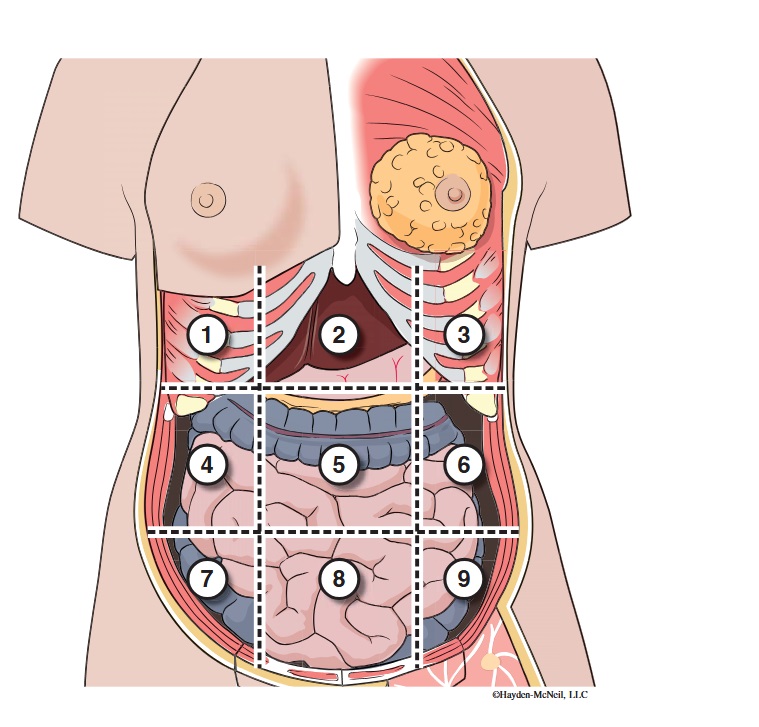

What abdominal region is labeled #1?

right hypochondriac

What abdominal region is labeled #2?

epigastric

What abdominal region is labeled #3?

left hypochondriac

What abdominal region is labeled #4?

right lumbar

What abdominal region is labeled #5?

umbilical

What abdominal region is labeled #6?

left lumbar

What abdominal region is labeled #7?

right iliac/ inguinal

What abdominal region is labeled #8?

hypogastric

What abdominal region is labeled #9?

left illiac/ inguinal

What organs are apart of the right hypochrondriac region?

right lobe of liver, gallbladder, right adrenal gland

What organs are apart of the epigastric region?

pyloric end of stomach, duodenum, pancreas

What organs are apart of the left hypochondriac region?

stomach, spleen, left adrenal gland

What organs are apart of the right lumbar region?

ascending colon, right kidney, portion of small intestine

What organs are apart of the umbilical region?

omentum, mesentery, small intestine

What organs are apart of the left lumbar region?

descending colon, left kidney, portion of the small intestine

What organs are apart of the right iliac/ inguinal region?

cecum of large intestines, appendix, right ovary

What organs are apart of the hypogastric region?

ileum, bladder, uterus

What organs are apart of the left iliac/ inguinal region?

sigmoid colon, left ureter, left ovary